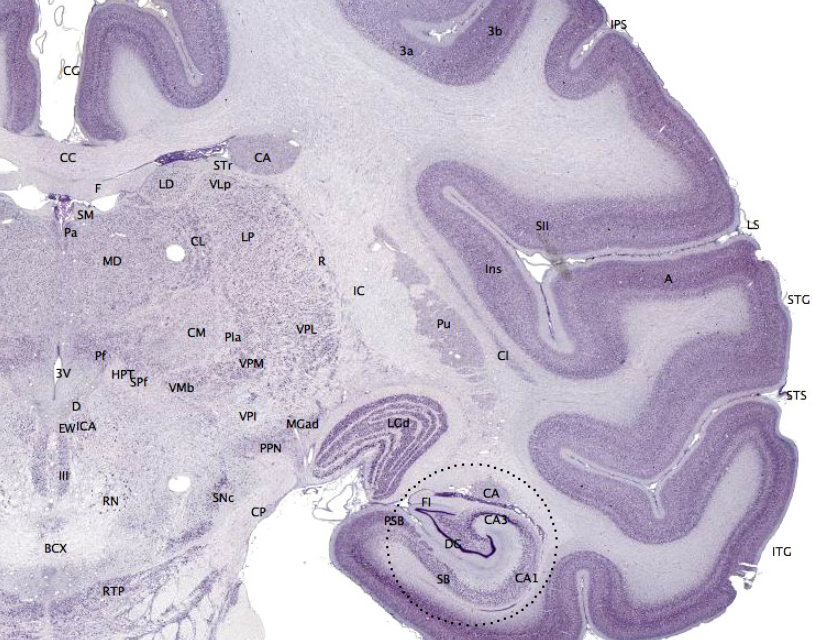

The hippocampus provides animals with a spatial map of their environment.[23] It stores information regarding non-egocentric space (egocentric means in reference to one's body position in space) and therefore supports viewpoint independence in spatial memory.[24] This means that it allows for viewpoint manipulation from memory. It is however, important for long-term spatial memory of allocentric space (reference to external cues in space).[25] Maintenance and retrieval of memories are thus relational or context dependent.[26] The hippocampus makes use of reference and working memory and has the important role of processing information about spatial locations.[27]

Blocking plasticity in this region results in problems in goal-directed navigation and impairs the ability to remember precise locations.[28] Amnesic patients with damage to the hippocampus cannot learn or remember spatial layouts and patients having undergone hippocampal removal are severely impaired in spatial navigation.[24][29] Monkeys with lesions to this area cannot learn object-place associations and rats also display spatial deficits by not reacting to spatial change.[24][30] In addition, rats with hippocampal lesions were shown to have temporally ungraded (time-independent) retrograde amnesia that is resistant to recognition of a learned platform task only when the entire hippocampus is lesioned, but not when it is partially lesioned.[31] Deficits in spatial memory are also found in spatial discrimination tasks.[29]

Large differences in spatial impairment are found among the dorsal and ventral hippocampus. Lesions to the ventral hippocampus have no effect on spatial memory, while the dorsal hippocampus is required for retrieval, processing short-term memory and transferring memory from the short term to longer delay periods.[32][33][34] Infusion of amphetamine into the dorsal hippocampus has also been shown to enhance memory for spatial locations learned previously.[35] These findings indicate that there is a functional dissociation between the dorsal and ventral hippocampus.

Hemispheric differences within the hippocampus are also observed. A study on London taxi drivers, asked drivers to recall complex routes around the city as well as famous landmarks for which the drivers had no knowledge of their spatial location. This resulted in an activation of the right hippocampus solely during recall of the complex routes which indicates that the right hippocampus is used for navigation in large scale spatial environments.[36]

The hippocampus is known to contain two separate memory circuits. One circuit is used for recollection-based place recognition memory and includes the entorhinal-CA1 system,[37] while the other system, consisting of the hippocampus trisynaptic loop (entohinal-dentate-CA3-CA1) is used for place recall memory[38] and facilitation of plasticity at the entorhinal-dentate synapse in mice is sufficient to enhance place recall.[39]

Spatial memories are formed after an animal gathers and processes sensory information about its surroundings (especially vision and proprioception). In general, mammals require a functioning hippocampus (particularly area CA1) in order to form and process memories about space. There is some evidence that human spatial memory is strongly tied to the right hemisphere of the brain.[60][61][62]

The function of NMDA receptors varies according to the subregion of the hippocampus. NMDA receptors are required in the CA3 of the hippocampus when spatial information needs to be reorganized, while NMDA receptors in the CA1 are required in the acquisition and retrieval of memory after a delay, as well as in the formation of CA1 place fields.[65] Blockade of the NMDA receptors prevents induction of long-term potentiation and impairs spatial learning.[66]

The CA3 of the hippocampus plays an especially important role in the encoding and retrieval of spatial memories. The CA3 is innervated by two afferent paths known as the perforant path (PPCA3) and the dentate gyrus (DG)-mediated mossy fibers (MFs). The first path is regarded as the retrieval index path while the second is concerned with encoding.[67]